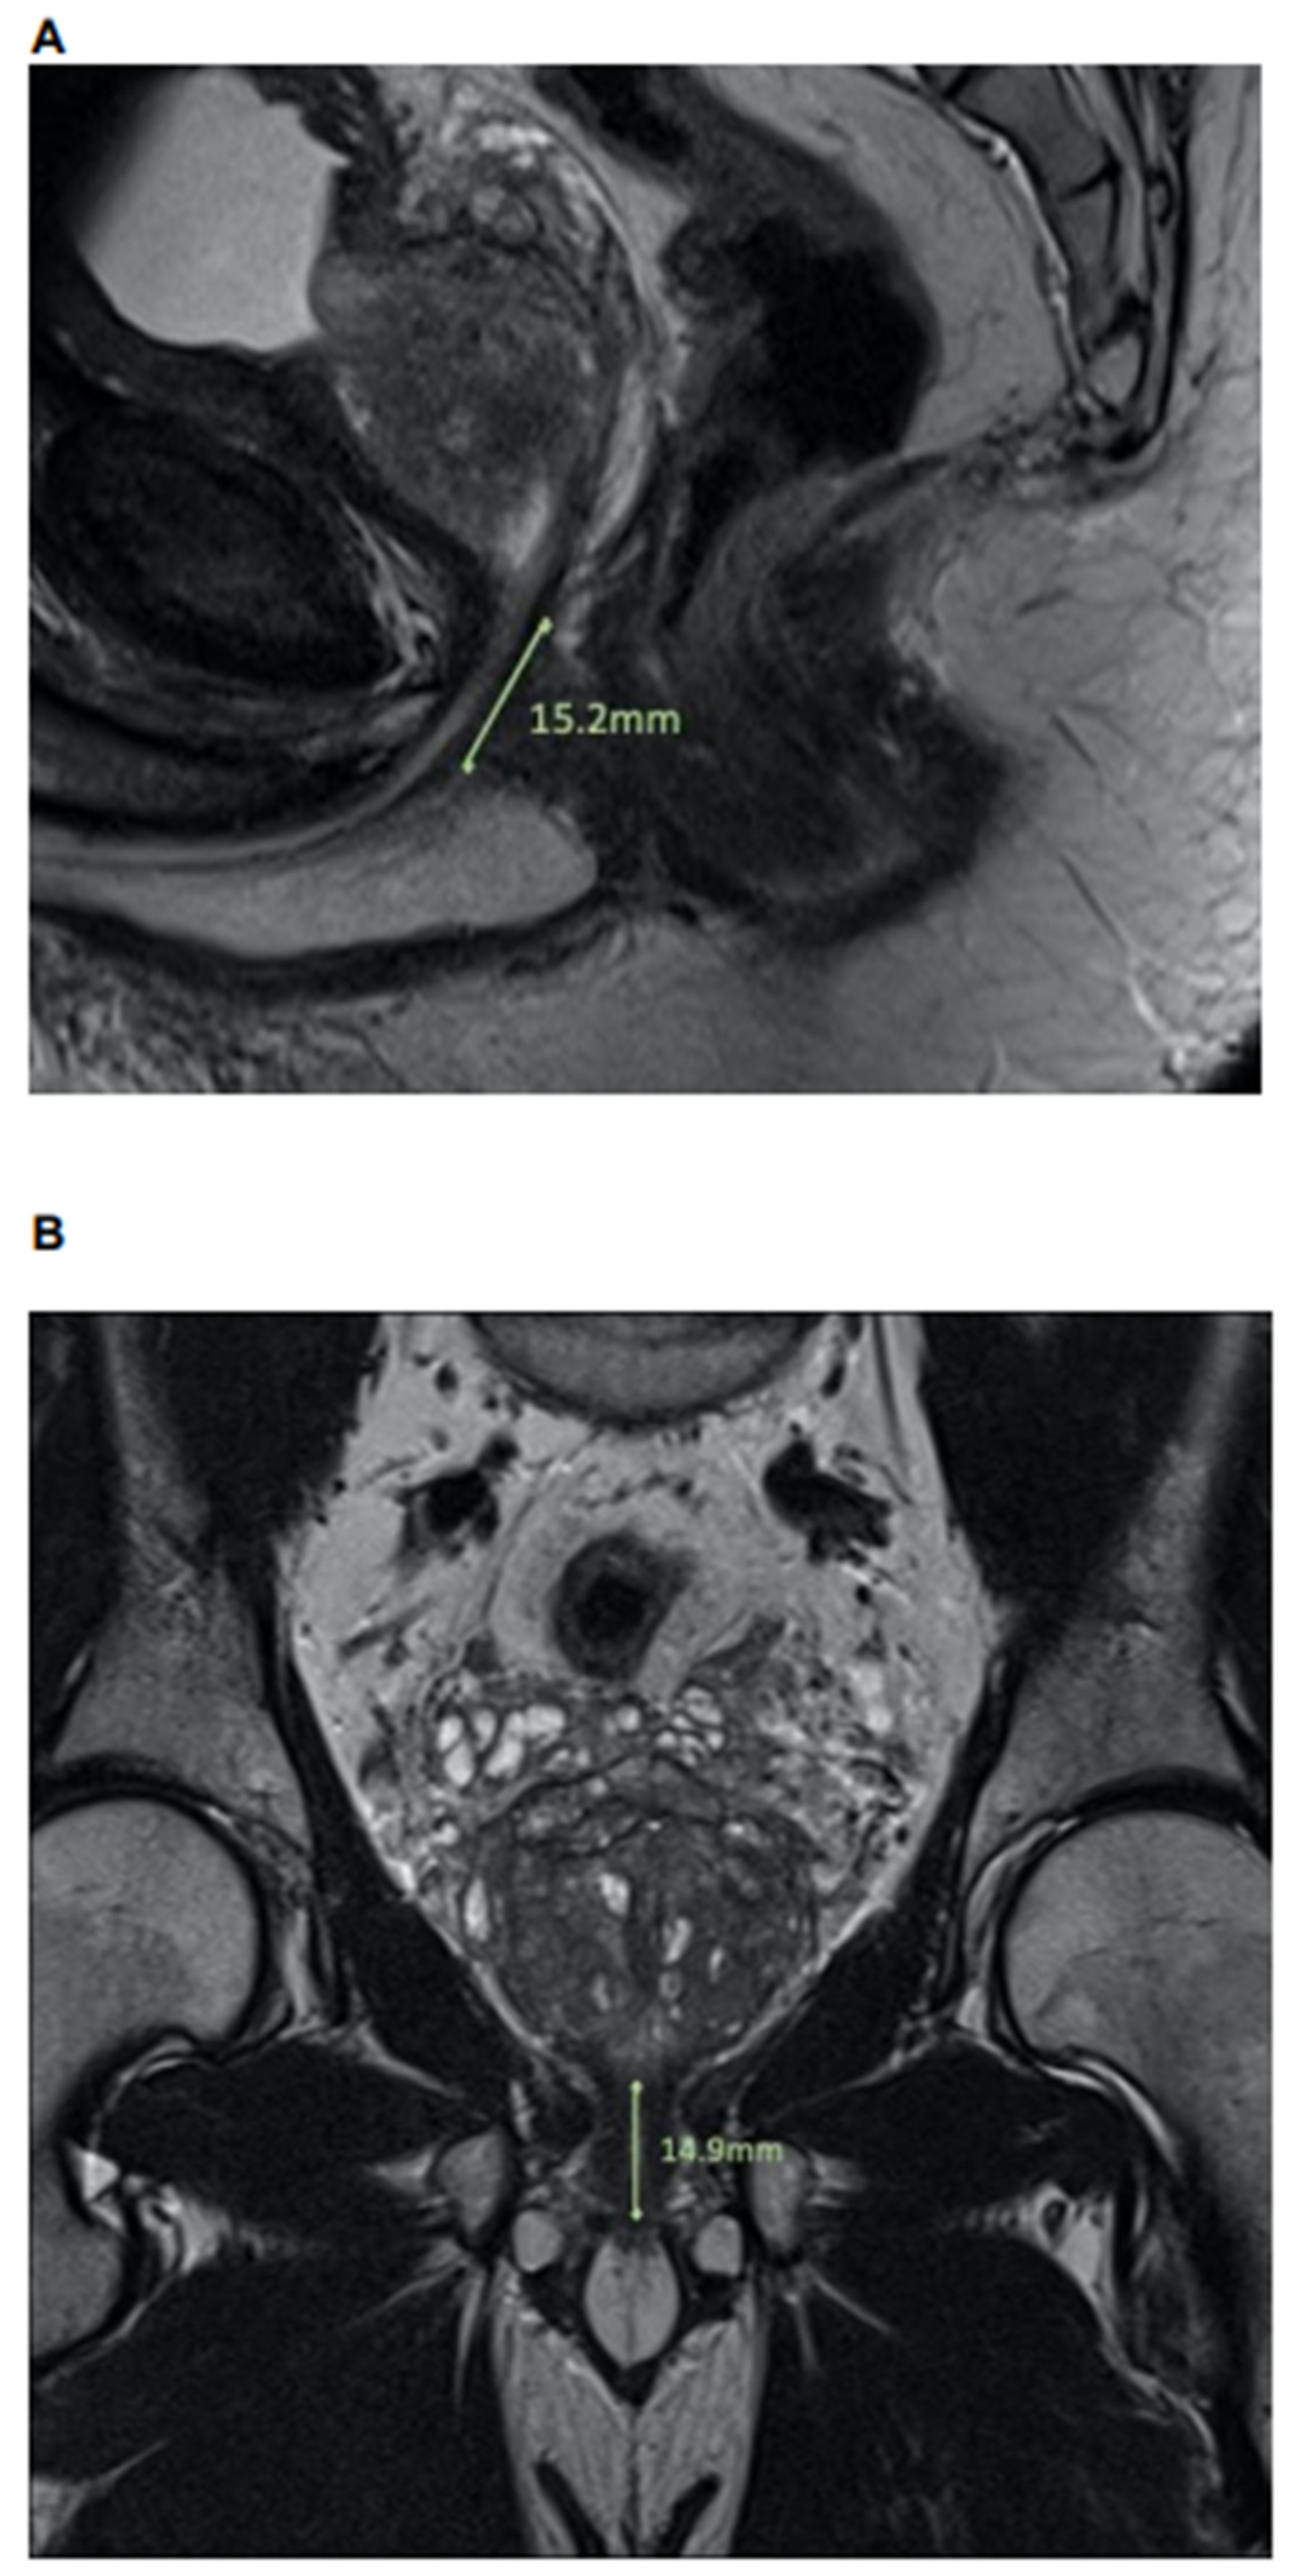

Length of urethral sphincter, coronal, in mm Median (IQR) | 14.7 (13.0, 16.7) | 15.0 (13.7, 17.1) | 14.5 (12.2, 16.2) | 0.2 |

Length of urethral sphincter, sagital, in mm Median (IQR) | 15.1 (12.8, 16.8) | 15.1 (14.1, 17.0) | 15.3 (10.8, 16.7) | 0.4 |